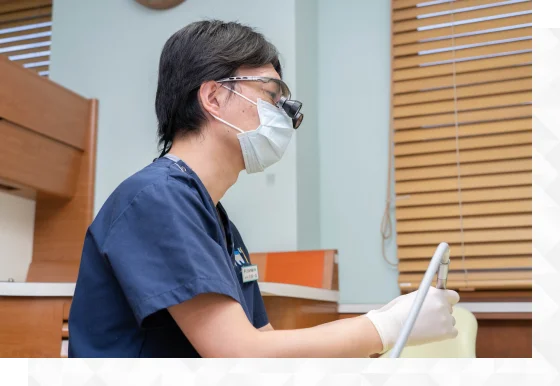

当院の歯周病治療

超音波スケーラーを用いたスケーリングが可能

当院では歯周病治療のスケーリングにおいて、超音波スケーラーを用いて処置いたします。超音波スケーラーは毎秒25,000~30,000サイクルでチップが振動して、歯の表面に付着した歯石を徹底的に取り除きます。先端設備を活用して、質の高い歯周病治療をご提供いたします。